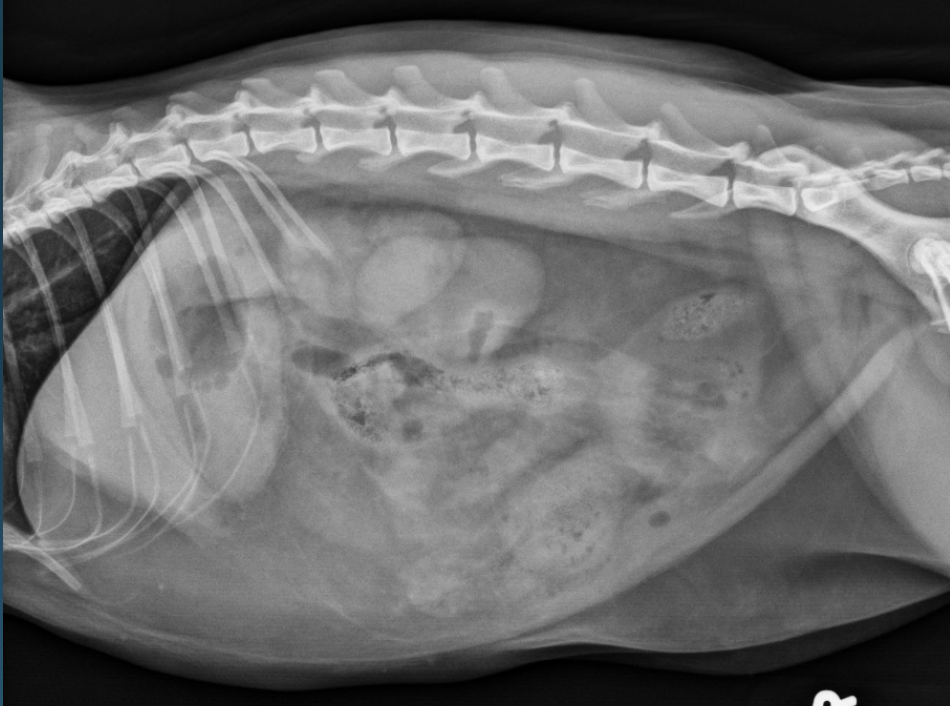

What is shown in this image?

A

normal abdomen in an obese cat